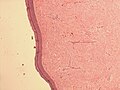

Features:[3]

- Superficial dermal lesion:

- Usu. lobulated or micronodular architecture - key feature.

- +/-Focal sheeting.

- Spindle/epithelioid morphology with pale eosinophilic cytoplasm - key feature.

- +/-Inflammation around lesion.

- +/-Surrounded by collagen.